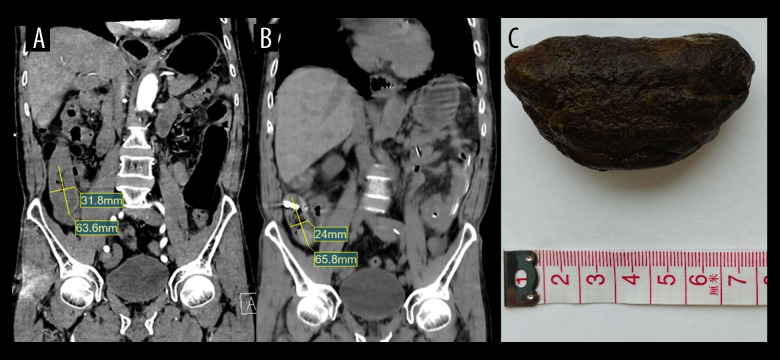

BACKGROUND Phytobezoar-induced small bowel obstruction presents significant management challenges, particularly in patients who either decline surgery or have contraindications. These concretions, predominantly composed of persimmon tannins, account for 0.4-4.8% of intestinal obstructions in endemic regions. While surgical intervention remains standard for complete obstructions, non-surgical approaches are increasingly explored for high-risk patients. Current dissolution therapies, including the Coca-Cola protocol, often require large fluid volumes that can exacerbate the obstruction. This study evaluated the efficacy of a novel treatment using low-volume sodium bicarbonate irrigation combined with catheter decompression. CASE REPORT Two elderly men (aged 73 and 74 years) with persimmon-induced obstructions refractory to conservative treatment underwent endoscopic intestinal catheter placement. Targeted 5% sodium bicarbonate irrigation (100 mL bid) with intermittent catheter clamping was administered. Clinical progress was monitored through serial imaging and symptom assessment. Both cases achieved complete obstruction resolution without surgery. Case 1 demonstrated CT-confirmed bezoar reduction within 10 days, with spontaneous passage. Case 2 expelled a 3×7 cm bezoar after 5 days of therapy. No procedural complications or biochemical imbalances occurred. The protocol synergized bicarbonate's mucolytic action (alkaline dissolution of phytobezoar matrices) with mechanical catheter decompression. CONCLUSIONS This first-reported combination therapy successfully resolved large phytobezoars (4-7 cm) within 5-10 days, establishing a safe alternative for candidates who either decline surgery or have contraindications. The method's efficacy stems from: 1) minimized fluid volume requirements (200 mL/day vs 500-3000 mL in Coca-Cola protocols), 2) direct bezoar contact via catheter-directed delivery, and 3) dual mechanical-chemical action.